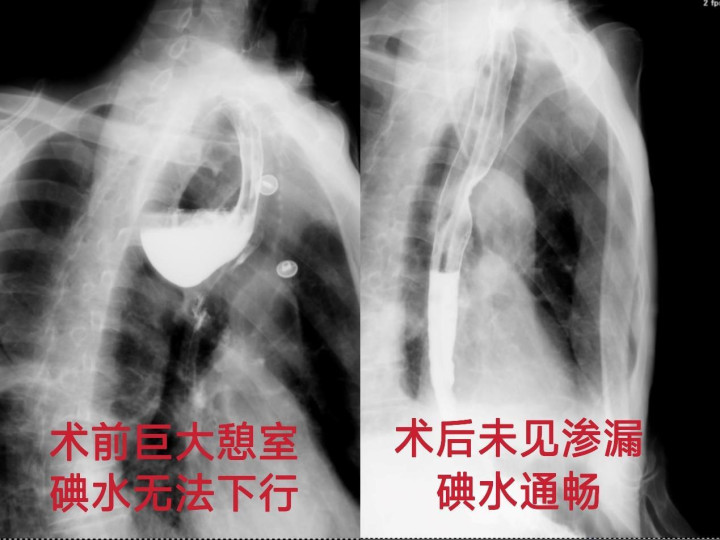

术后,胸外科医护团队为张先生制定了阶梯式精细化营养支持方案及围术期并发症管理计划。术后一周,碘水造影显示患者食管通畅,吻合口完整无渗漏;颈部切口愈合后仅留下一条细微痕迹,几乎隐匿于皮肤纹理之中,真正实现了疾病治愈与外观维护的双重目标。2026年元旦当天,张先生带着重生的喜悦,返回河北老家。